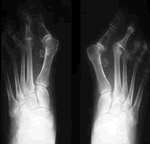

Fotos Dedos Hallux

Hallux Valgus Hallux Valgus Hallux Valgus Hallux Valgus